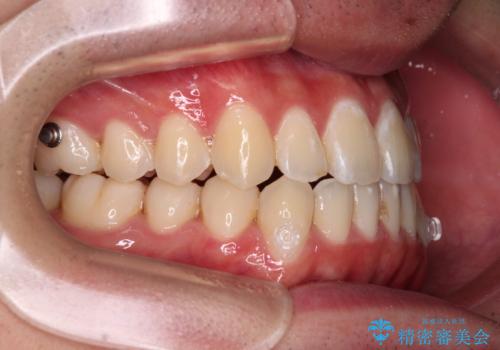

受け口傾向の骨格であり、前歯はクロスバイトまたは切端咬合となっており、叢生は警備であったため、下顎を中心に歯列全体の後方移動を行い、IPR(歯と歯の間を削る)によってデコボコが解消するように設計し、インビザラインにより治療を行うこととしました。

受け口傾向のインビザライン矯正は比較的治療を行いやすいため、きれいに仕上げることができました。舌の突出癖が顕著であったため、改善のためのトレーニングをしっかりと行っていただきました。